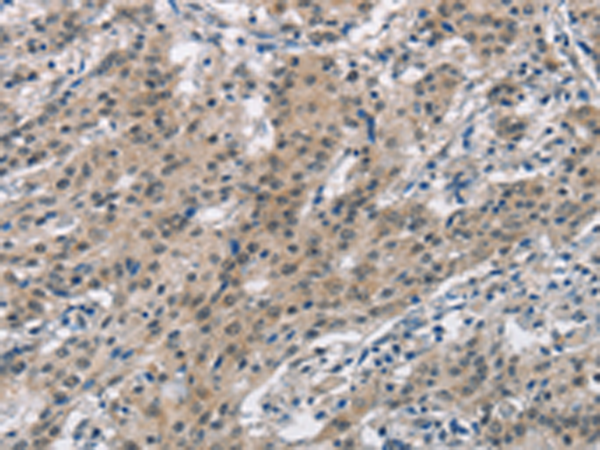

分类: 科研抗体货号: P11572别名: PD1; NACP; PARK1; PARK4应用: IHC反应种属: Human, Mouse, Rat